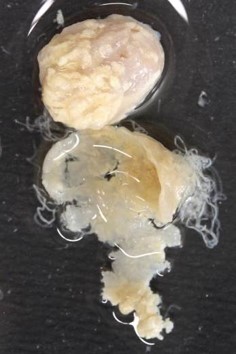

- Skin nodules of various sizes in the dermis or subcutaneous tissues contain adult worms

- Nodules (onchocercomas) contain live or calcified adult worms